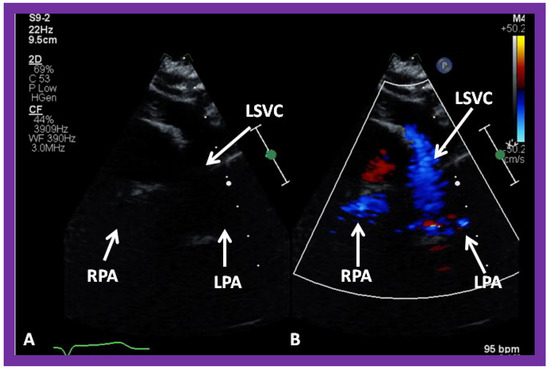

In patients who have a persistent left SVC entering the heart via the coronary sinus, bilateral bidirectional Glenn procedures are performed, especially if the inter-connecting left innominate vein is small or absent. An example of left sided bidirectional Glenn is shown in Figure 30. In subjects who have infrahepatic interruption of the inferior vena cava (IVC) with azygos or hemiazygos continuation (into the right or left SVC, respectively), a Kawashima procedure is performed. In these patients, echocardiographic imaging of the Glenn/Kawashima is similar to that of regular bidirectional Glenn (Figure 25, Figure 26 and Figure 27).

Figure 30. (A,B) Selected video frames from suprasternal notch view demonstrating left sided bidirectional Glenn shunt. In (A), the right (RPA) and left (LPA) pulmonary arteries are faintly seen by 2D. On color Doppler study, the visualization is slightly better (B). LSVC, left superior vena cava.